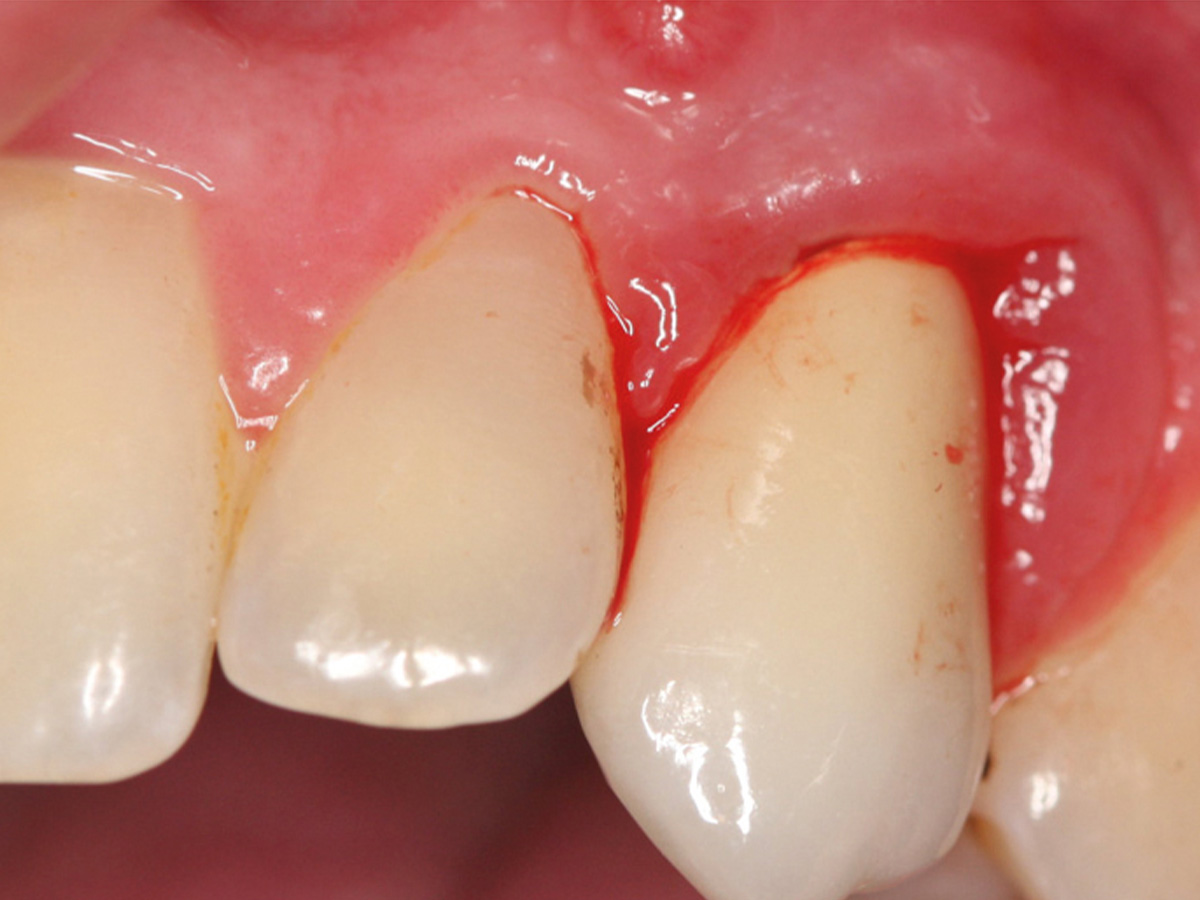

Abbildung 1

Klinische Ausgangssituation lateral, spontane Blutung.